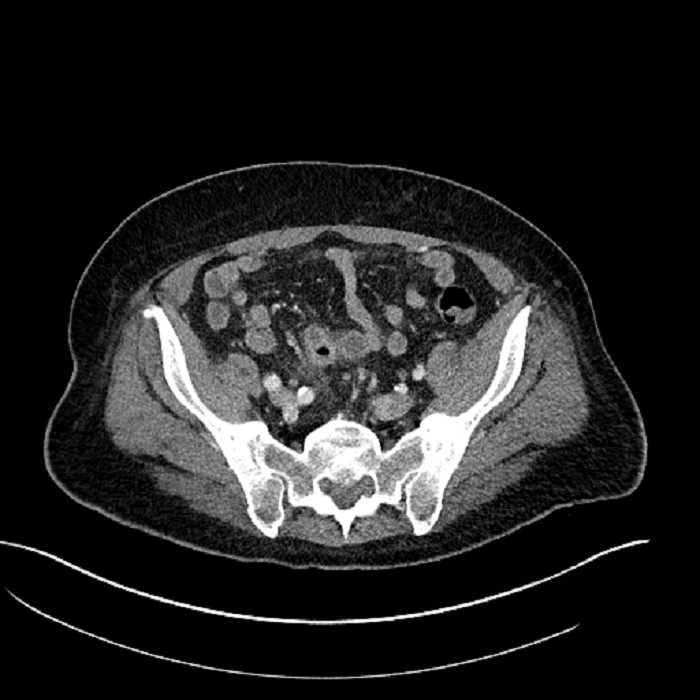

• Mild mural thickening of a segment of the sigmoid colon with adjacent fat stranding and a 1.5 cm fluid and gas collection along the tip of an inflamed diverticulum

• Loss of the normal fat plane between this collection and adjacent loops of small bowel, which demonstrate mural thickening

Acute sigmoid diverticulitis complicated by a small contained perforation and a large abscess in the right hepatic lobe. Additional small subcapsular abscesses along the anterior margin of the left hepatic lobe.

Additionally, loss of the normal fat plane between the peridiverticular collection and adjacent thickened loops of small bowel raises the potential for an enterocolonic fistula.

Hepatic abscess showing the double target sign with low density internally surrounded by a thin inner enhancing rim (red arrow) and ill-defined outer low density rim (yellow arrow). Blue arrow indicates an internal septation. Red arrows: additional smaller subcapsular abscesses. Red arrow: focal contained perforation associated with diverticulitis.